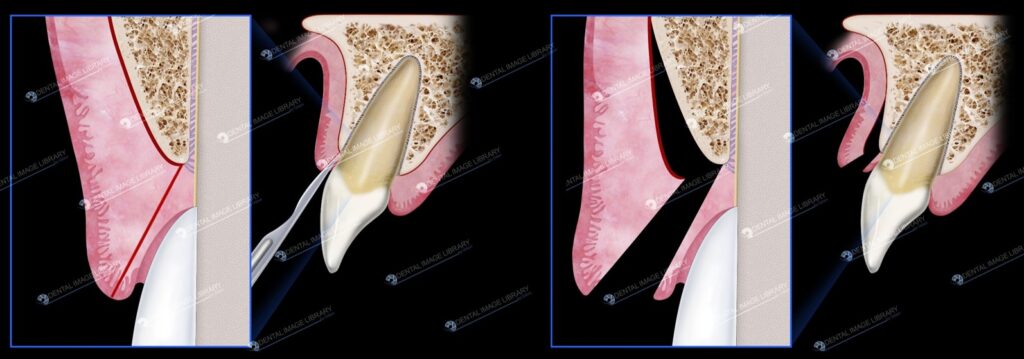

- Vạt dày toàn phần nghĩa là đường rạch hoàn toàn xuyên qua mô nướu cho đến khi chạm xương. Khi lật vạt lên, lớp màng xương sẽ bị bong ra khỏi bề mặt xương ổ răng và sử dụng xương làm điểm tựa (hình 2-4). Vạt này được sử dụng thường xuyên nhất trong phẫu thuật xâm lấn nha chu.

- Vạt dày bán phần (hình 2-5) được tạo ra bằng cách rạch qua mô nướu nhưng không tiếp xúc với xương. Lật vạt niêm mạc lên để tách niêm mạc ra khỏi màng xương, phần này được để lại tại chỗ xương bên dưới. Vạt này được sử dụng phổ biến nhất cho các thủ thuật ghép niêm mạc nướu hoặc chuyển vạt từ cuống.